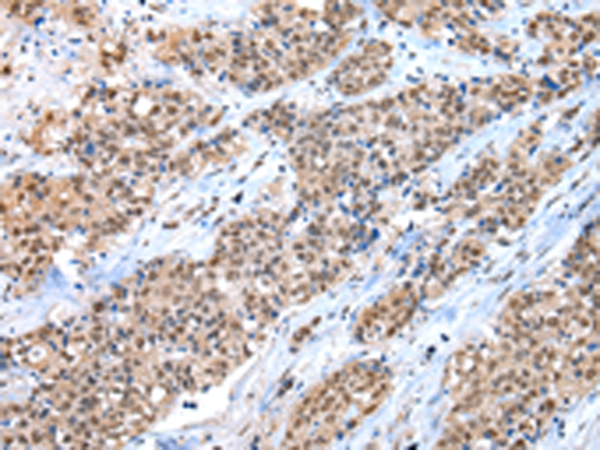

分类: 科研抗体货号: P12476别名: FIC; MARC; MCP3; NC28; MCP-3; SCYA6; SCYA7应用: IHC反应种属: Human